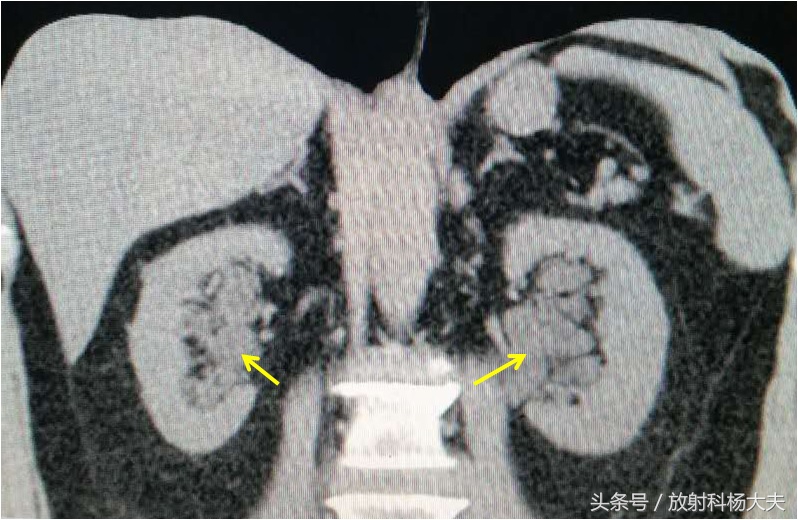

未注射对比剂时,双肾盂区可见液体密度,非常像肾积水

注射对比剂后,可以看到红箭为充盈对比剂的正常肾盂。黄箭为肾盂旁囊肿。